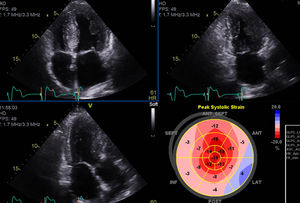

The following year, he developed NYHA class II to III congestive heart failure (HF), requiring uptitration of diuretics. The repeat echocardiogram showed moderate concentric left ventricular hypertrophy, with preserved ejection fraction but an abnormal global longitudinal strain and elevated filling pressures (Figure 3). He repeated the coronary angiography which excluded CAD progression. He underwent a 99mTc-DPD scintigraphy that revealed significant myocardial tracer uptake, diagnosing TTR amyloid infiltration (Figure 4). He was stabilized with medical therapy and kept under close follow-up, requiring antianginal therapy uptitration for exertional microvascular angina.